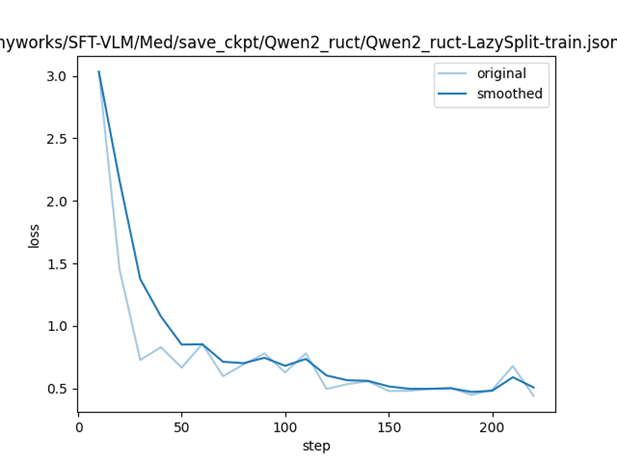

微调loss曲线:

微调loss曲线: